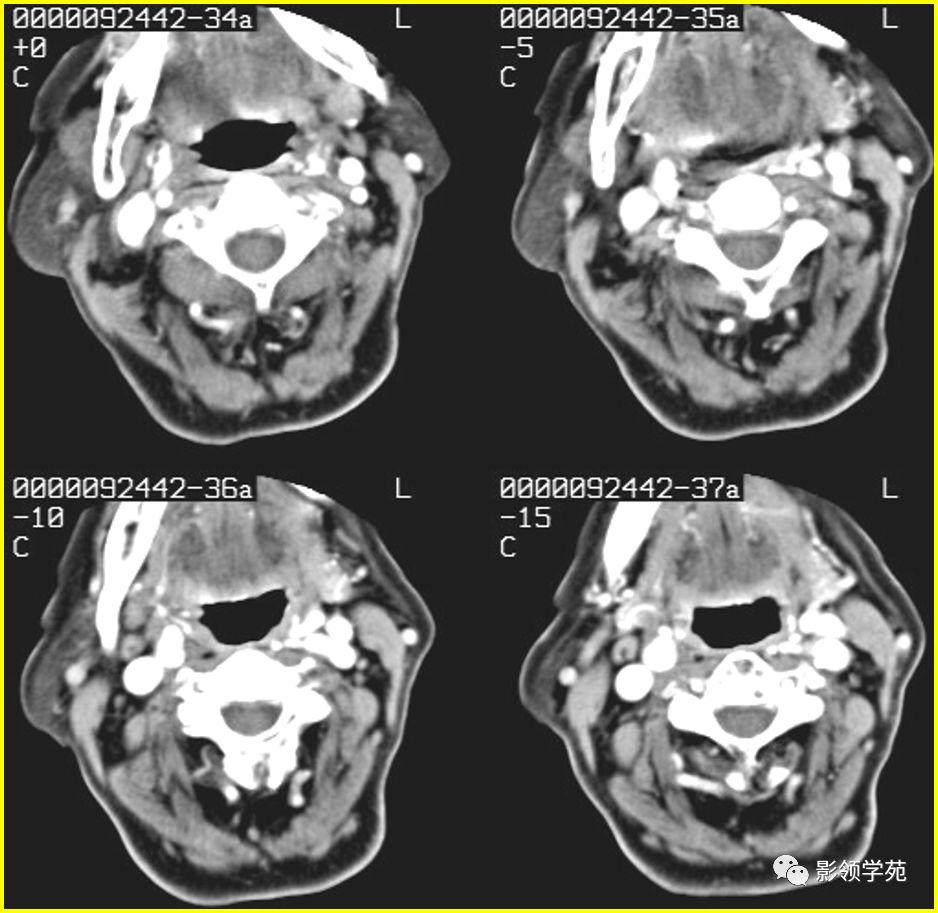

- 腮裂囊肿